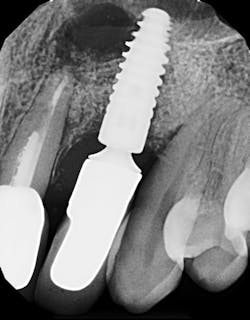

Detecting excess cement can usually be done with a radiograph if the cement is located in the interproximal region and is radiopaque (figure 4).